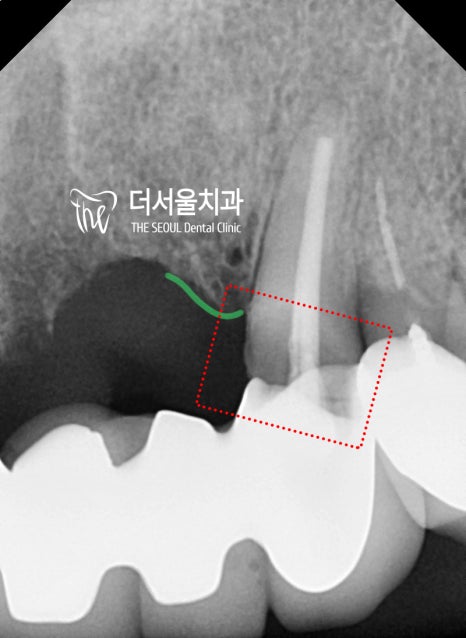

치근단 엑스레이를 보면

이 분께서 왜 저를 찾아오셨는지 알 수 있습니다.

이 2가지의 원인 때문에 오시게 된 거고,

이미 구강 내 상당한 통증을 느끼고 계셨습니다.